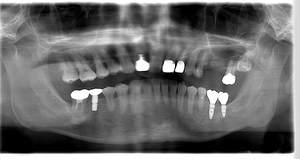

レントゲン写真

- Befor

- After

| 年齢 | 50代・男性 |

| 主訴 | 左上7番 左下5番7番 |

| 治療内容 | ・インプラント埋入 ※1:GBR(骨造成)・・・骨再生誘導法。骨の高さや厚みを人工骨や人工膜などを使用し再生する方法 |

| 治療費 | 合計:1,809,500円(税込) ■内訳 ・左上7番 ・左下5番7番 |

| 治療期間 | 左上7番約1年 左下5番7番約10ヵ月 |

| 治療方針 | 左上7番は昔他院で被せものをしており、被せものの中が歯ぐきの中まで虫歯になっていたため抜歯せざるを得ない状態だった。抜歯と同時に骨造成を行い、骨が出来るまで4ヵ月待ってからインプラントを埋入した。 ※2ポンティック・・・歯のない部分を補うダミーの歯。 |

| 担当者所見 | 元々金属の被せものが多く入っていたため、2次カリエス※3が多かった。今回は金属ではなく、ジルコニアを使用し、2次カリエスにならないよう、患者様にはブラッシング指導とメンテナンスの重要性をお伝えした。 ※3二次カリエス・・・詰め物や被せものを入れた歯が虫歯になること。 |